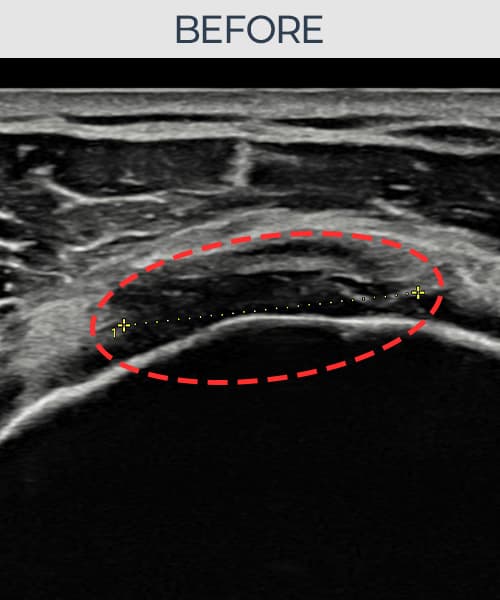

[촬영시기:21.11.04~21.11.09]

[석회분쇄흡입술] 우측 어깨 극심한 야간 통증으로 수면이 불가능해진 50대 여성 환자로, X-ray에서 우측 극상근건 내 석회 침착이 확인되어 석회분쇄흡입술을 시행하였습니다.